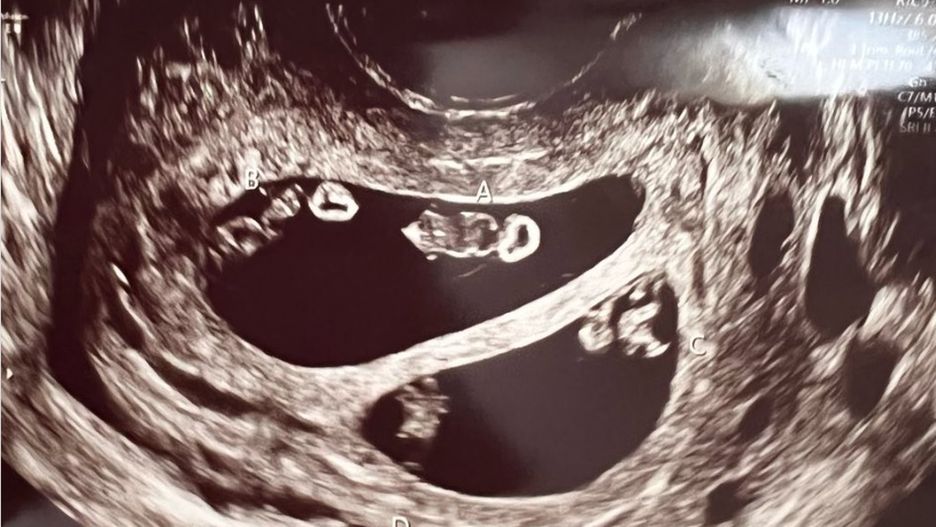

Jak się okazało, po wykonaniu badania USG, kobieta miała urodzić więcej niż jedno dziecko. Nie byłoby w tym nic dziwnego, gdyby nie fakt, że w jej brzuchu rozwijały się dwie pary bliźniaków. Wprawdzie takiego rodzaju ciąże się zdarzają, ale prawdopodobieństwo ich wystąpienia wynosi jeden na 10 milionów przypadków.

- Lekarz patrzył w monitor, później spojrzał się na nas i mówił ciągle "to niesamowite, jak to możliwe" - opowiada Ashley.

Podczas USG okazało się, że jest w podwójnej ciąży bliźniaczej

Podczas USG okazało się, że jest w podwójnej ciąży bliźniaczej © FB